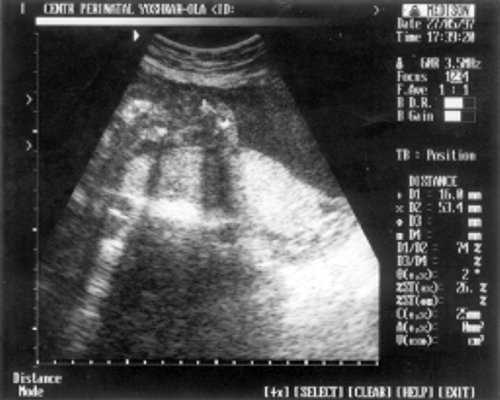

- Плечевая кость = 16 мм - 14,5 нед. (рис. 3)

Рис. 3. УЗИ плода - плечевая кость.